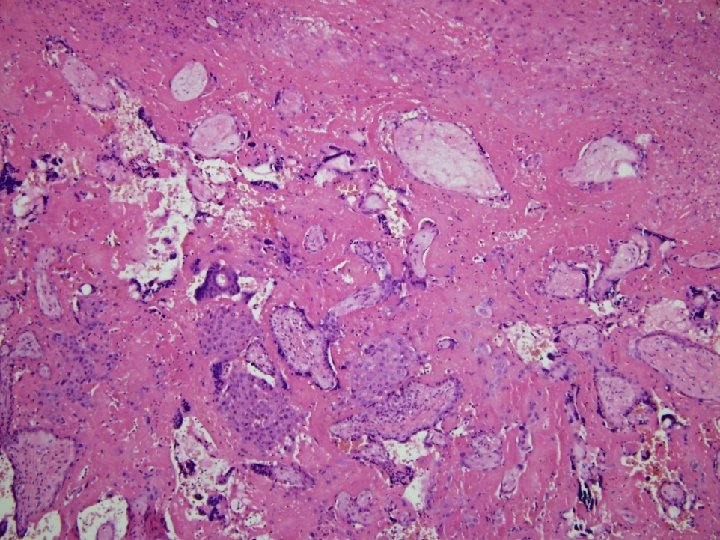

MFD histologie • Choriové klky jsou zality eozinofilně se barvící hmotou (fibrinoid) – V časné fázi jsou klky intaktní – V pozdní fázi • Degenerace a zánik syntitiotrofoblastu • Fibróza klků, hyalinní dystrofie • Obliterace cév - avaskulární klky – Proliferace extravilosního trofoblastu (X bb. ) v masách fibrinoidu event. tvorba cyst • Zůstavají nepostižená místa s volným intervilosním prostorem

MFD (Gitterinfarkt) • 1967 Benirschke, Driscoll • Názvosloví: – – – MFI = Maternal floor infarction (USA) MFD = Massive perivillous fibrin deposition (VB) Massive perivillous fibrinoid Gitterinfarkt (Něměcko) Mřížovitý/síťový infarkt (Jurkovič) • Nadměrné ukládání fibrinoidu v placentě – MFI: v bazální/mateřské ploténce – MFD: depozita v intervilosním prostoru celé výšky placenty transmurální • Některými autory pokládány za zvláštní, i když příbuzné, patologické jednotky – Nejedná se o ischemickou koagulační nekrózu, infarktu placenty se podobá jen ztuhnutím postižené tkáně.

Fibrinoid • Extracelulární fibrinu podobná hmota – Směs • fibrinu krevního séra (fibrin-type fibrinoid) • sekrečních produktů extravilosního trofoblastu (matrix-type fibrinoid): kolagen IV, laminin, fibronektiny, merosin, heparansulfát aj. – PAS +, modrý trichrom (světle modrá/červená), slabě Kongo červeň (nejde o amyloid), barvení na fibrin fokálně pozitivní – Univerzální součást lidských placent – Množství fibrinoidu stoupá k termínu porodu – Subchoriálně (subchoriální pseudoinfarkty) perivilosně, intravilosně, v mateřské ploténce, marginálně – Neznámá funkce